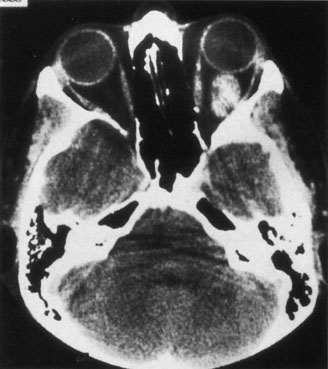

There are no pathognomonic ultrasonography, CT, or MRI findings. A-scan ultrasonography shows well-delineated regular structures with low internal reflectivity and minimal attenuation owing to the congested pools of blood in the dilated veins. Doppler demonstrates flow within the lesion.58 Computed tomography may show abnormally dilated, irregular veins with uniform contrast enhancement or, when there has been hemorrhage, multilobular lesions.58 As the VFM may not be visualized when collapsed, direct coronal scans should be obtained in the prone position or during the Valsalva maneuver to distend the lesions (Fig. 14). Spiral CT with a single breath-holding technique may be useful in confirming an increase in size of the lesion during the Valsalva maneuver.104 The majority of venous malformations typically occupy the superomedial orbit in the area of the superior ophthalmic vein, followed by the inferolateral quadrant.95,104 In their study of 158 patients with NFM and VFM, Wright and colleagues found 45% with phleboliths.95 Enlargement of the affected orbit also may be seen.95 Obtaining MRI scans before and during a Valsalva maneuver may show distensibility, and uniform enhancement occurs.58 Venography is seldom used now because of the availability of other imaging modalities. Carotid angiography may demonstrate the VFM and can detect venous enlargement consequent to arteriovenous shunting.

Fig. 14. Orbital venous flow malformation. Axial computed tomography scan showing an ill-defined, dense, inhomogeneous orbital lesion with the patient in a supine position (A). Note the phlebolith, which indicates venous stagnation. As the venous flow malformation distends with the patient in the prone position, the lesion enlarges (B). (Courtesy of Dr. John V. Linberg, University of West Virginia, Morgantown, WV)